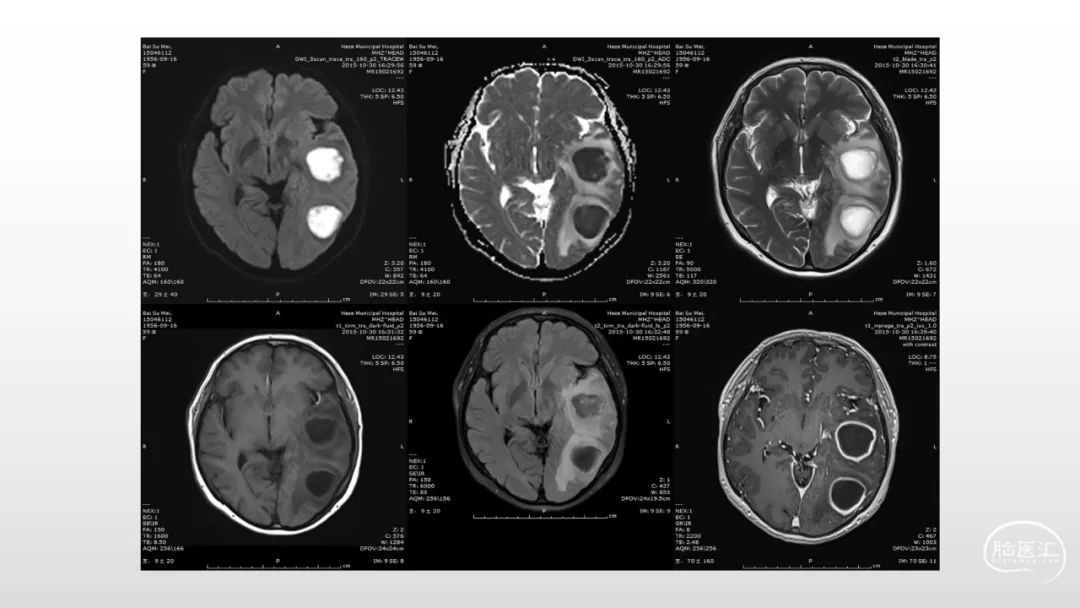

颅脑影像诊断基础知识讲座:感染和免疫性疾病1